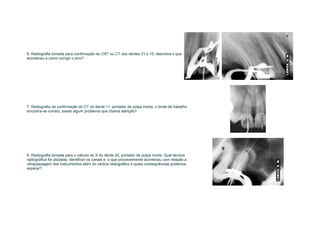

4. Radiografia do dente 26 para prova dos cones principais de obturação, qual técnica

radiográfica foi utilizada, por que e identifique os canais, a partir da mesial?

6. Radiografia tomada para confirmação do CRT ou CT dos dentes 21 e 15, descreva o que

aconteceu e como corrigir o erro?

7. Radiografia de confirmação do CT do dente 11, portador de polpa morta, o limite de trabalho

encontra-se correto, existe algum problema que chama atenção?

8. Radiografia tomada para o cálculo do X do dente 25, portador de polpa morta. Qual técnica

radiográfica foi utilizada, identificar os canais e, o que provavelmente aconteceu com relação a

ultrapassagem dos instrumentos além do vértice radiográfico e quais consequências podemos

esperar?

A. dente 46, PM, RX de confirmação do                    B. dente 36, PM, RX de confirmação do                C. dente 47, PV, RX de confirmação do

CT, o que podemos concluir?                              CT, o que podemos concluir?                          CT, o que podemos concluir?